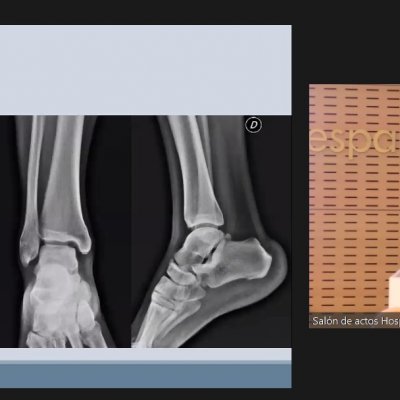

El Dr. Vilá ha destacado la importancia de un buen diagnóstico para un tratamiento individualizado con la elección de la técnica más apropiada para la reparación del tendón. Es fundamental analizar las características del paciente en la exploración, apoyándose de las pruebas complementarias necesarias para valorar la calidad tisular, la hiperlaxitud, la presencia de desaxaciones (alteración o desviación del eje normal de la articulación) y tener en cuenta factores como el elevado IMC (índice de masa corporal), la realización de actividad deportiva intensa o haber padecido más de 3 esguinces en el último año.

A continuación el Dr. Tomás Losa, médico residente R4, ha sido el encargado de presentar un caso práctico a nuestro invitado para conocer su punto de vista.